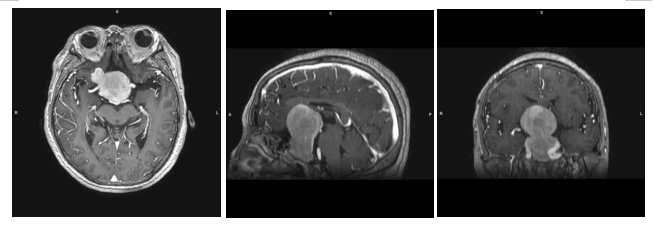

在瑞金医院神经外科,头颅磁共振的检查结果印证了医生的预判,姚阿姨颅内确有一个小苹果似的垂体肿瘤(53*45*59mm),因为肿瘤压迫到了视神经等才会引发上述症状。手术切除肿瘤是当务之急!

手术前